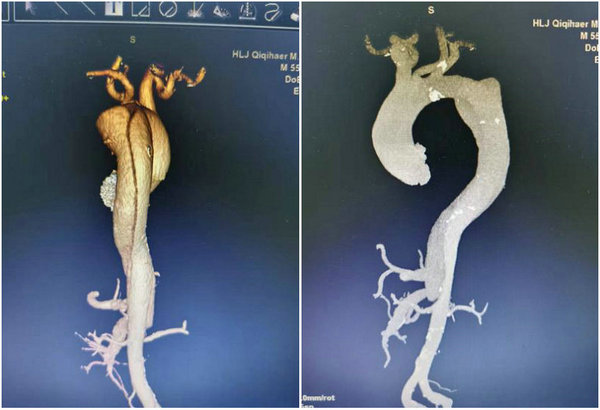

患者术前CTA检查提示

支架植入前(左)与植入后对比